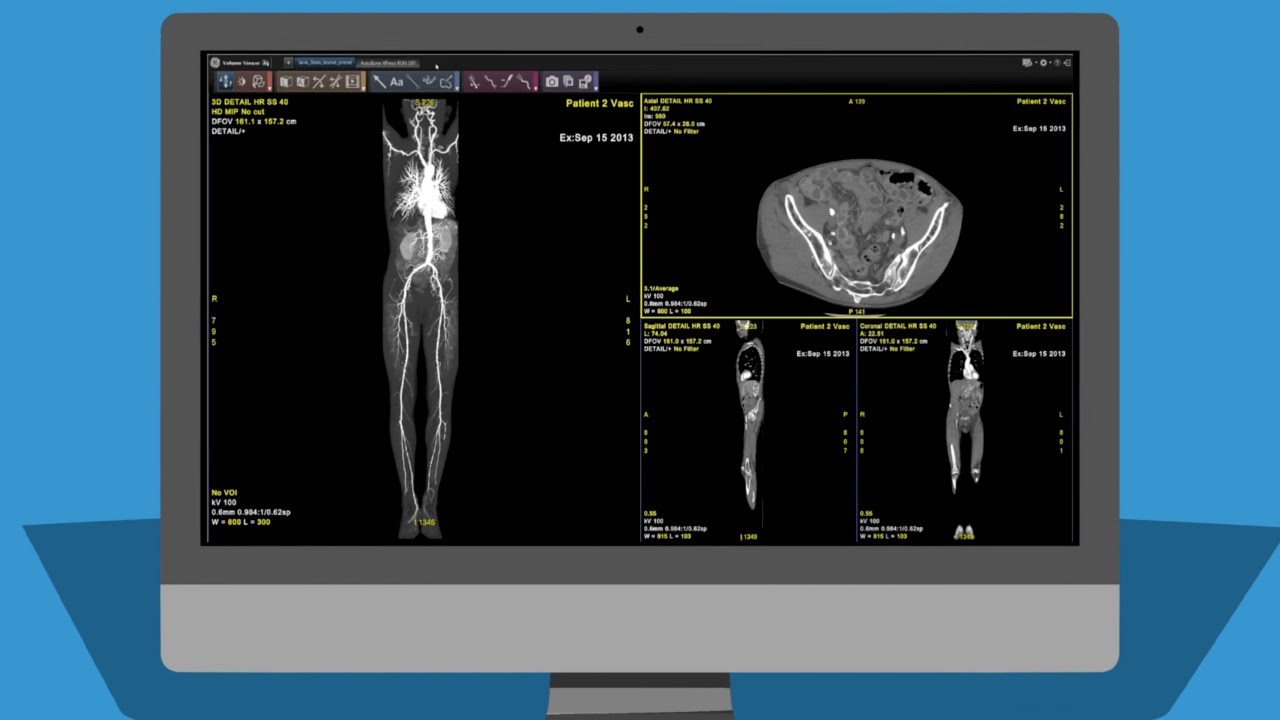

axial3D, a medical manufacturing service provider headquartered in Northern Ireland, is providing Newcastle Hospitals NHS Foundation Trust with an on-site 3D printing lab. Housed at the Royal Victoria Infirmary, one of six potential beneficiaries of the facility, the lab will be used to produced patient-specific models for pre-surgical planning.